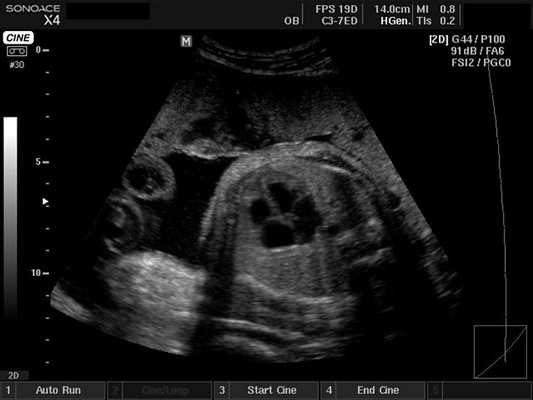

Плод - сердце, B-режим

[EN] Эхограмма №413: Сердце плода в B-режиме.

Изображение получено с помощью УЗ сканера SonoAce-X4 (снят с производства).